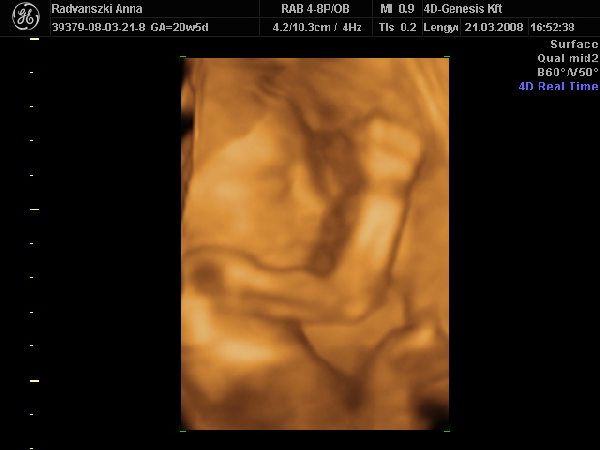

A mi kis manónk elég érdekeset produkált a mai UH-n. Eddig mindig fent volt a feje, most sikerült úgy fordulnia (ma reggelre), hogy a feje egészen lent volt, a medencecsontomnál. Úgy befúrta magát oda, és a két kezével takargatta magát, hogy alig láttuk a pofiját. Aztán nagyon nekikészült egy bukfencnek, vagyis próbálkozott átfordulni, a kis lábaival meg csak úgy taposott a méhfalon, de mindig lecsúszott a lába. Pedig nagyon drukkoltunk neki! Majd' meg zabáltam, olyan kis édes volt, ahogy próbálkozott...

Aztán egy idő után elfáradt, lemondott a fordulásról, kényelembe helyezkedett, és alaludt. Na a nagy ficergésnek köszönhetően legalább meg tudtuk utána nézni az arcát.

pofika